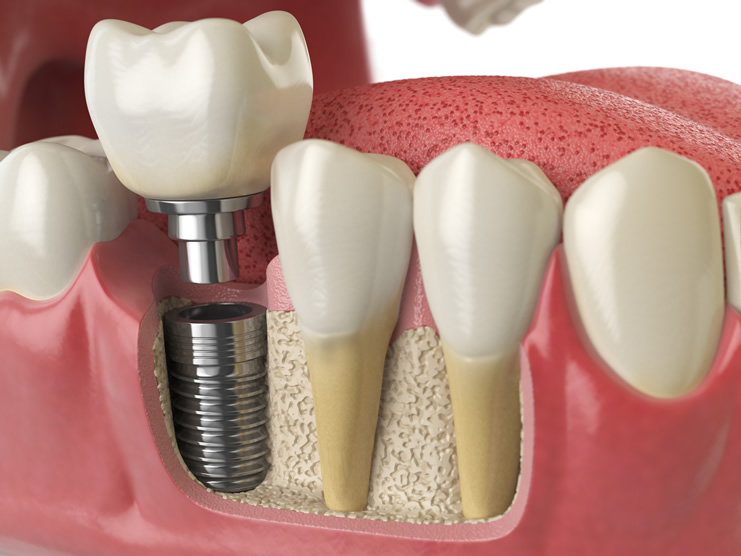

Što je implantat?

Implantat je zapravo zamjena za korijen zuba. Riječ je o vijku točno određene veličine koji se ugrađuje u kost čeljusti. On je izrađen od titana, plemenitog materijala, jedinog kompatibilnog sa ljudskom kosti. Odluka o postavljanju implantata donosi se na temelju digitalnog ortopana i kompjuterizirane tomografije (CT-a), odnosno snimke čeljusti. Implantologijom se može nadomjestiti jedan ili više zuba, a implantat je temelj, ili bolje rečeno, nosač za protetske nadomjestke. Na implantate možemo pričvrstiti proteze i mostove, ali jedan implantat može nadomjestiti i samo jedan zub ukoliko samo jedan zub manjka u zubnom nizu.